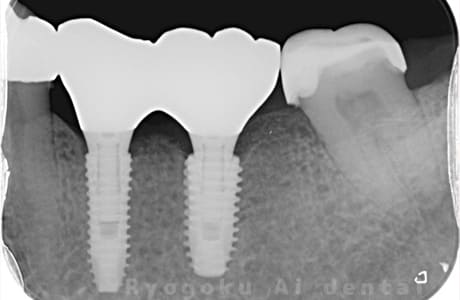

Case03

-

術前

- 原因

- 歯根破折

- 治療内容

- インプラント治療

- 治療費用

- 1,200,000円

左下の歯が腫れているとのことでご来院された患者様です。歯が割れていたため、抜歯となり、2本分歯がなくなったため、インプラントを2本入れました。手術時の痛みもなく、大きなトラブルもなく、非常に満足されています。

<リスク・副作用>

治療後、痛みや違和感、出血、腫れなどが出る事があります。喫煙者、糖尿病などの方の場合、歯が生着しない場合があります。